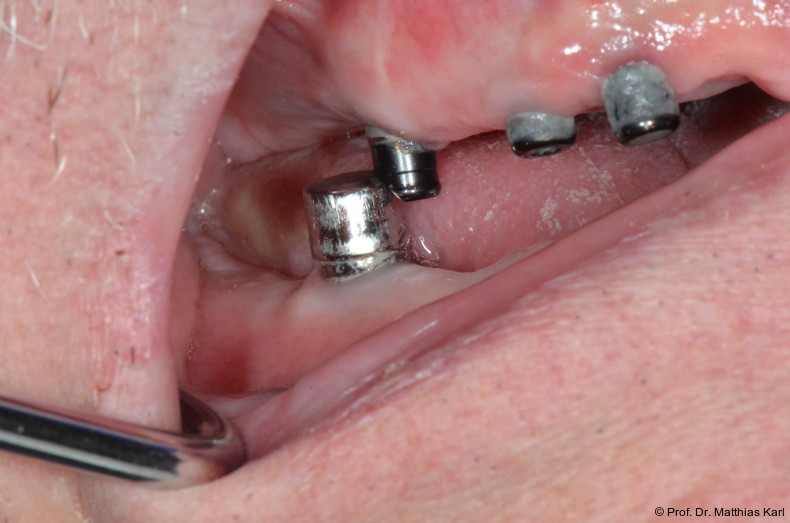

Für die einzelnen Verankerungselemente werden weit gestreute Haftkräfte berichtet, wobei der Haftkraftverlust das dominierende klinische Problem15 darstellt und zu wiederholten Interventionen führt.12, 13 Dies tritt insbesondere bei nicht parallel inserierten Implantaten auf, weshalb die Industrie sogenannte „extended range“ Verankerungselemente anbietet, die Dispa­rallelitäten kompensieren sollen. Gemäß einer retrospektiven Studie mit dreijähriger Beobachtungsdauer gelingt dies jedoch nicht.9 Ein weiterer Faktor dabei scheinen Übertragungsfehler der Patientensituation auf ein Labormodell zur Herstellung des Zahnersatzes zu sein.7

Eine randomisierte klinische Studie zu implantatgestützten Unterkieferdeckprothesen beschrieb den Verschleiß der Verankerungselemente als häufigste Komplikation.1 Ähnliche Ergebnisse werden aus einer randomisierten klinischen Studie an 18 Pa­tienten über neun Jahre Beobachtungsdauer mit 136 prothetischen Komplikationen berichtet.11 Dies wird ebenfalls von einer retrospektiven Studie an Kugelkopfankern bzw. Locatoren gestützt, welche Behandlungsnotwendigkeiten aufgrund von Verschleiß des Verankerungselements als häufigste Komplikation beschreibt.2 Ein hoher Anteil der nötigen Interventionen scheint dabei bereits in der Anfangsphase bis zu einem Jahr aufzutreten, was mit der Findung einer für den Patienten adäquaten Haltekraft assoziiert sein dürfte.3, 15